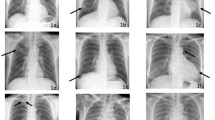

Changes in the CR interpretation performance of ED physicians, stratified by DLCR use, are presented in Table 2. There was a significant difference in the overall AUROC for CR interpretation among ED physicians working with DLCR when compared to those working without DLCR (P < 0.001). Other performance indices, including sensitivity, specificity, and accuracy of CR interpretation, in overall ED physicians were also significantly different, depending on DLCR use (P < 0.001, 0.015, < 0.001 respectively). After using DLCR, the sensitivity and accuracy of detecting abnormalities on CRs increased significantly in all ED physicians, while the AUROC values increased significantly except for those of one board-certified ED physician.

Sensitivity and accuracy estimates were significantly different between physicians who did and did not use DLCR, regardless of their level of experience; meanwhile, the AUROC and specificity values showed significant differences only in the inexperienced ED physician group (Table 3).

Table 4 summarises the findings on clinical decision-making consistency, according to DLCR usage. The overall kappa value was 0.902 (95% CI 0.884–0.920); the corresponding values for the experienced and inexperienced groups were 0.956 (95% CI 0.934–0.979) and 0.862 (95% CI 0.835–0.889), respectively; these estimates were significantly different (P < 0.001). Overall, a total of 126 clinical decisions changed after using DLCR. Of these, 48 decisions were changed from ‘unclear’ to ‘clear’ impression for ED disposition. These kinds of changes in clinical decisions were significantly more frequent among inexperienced physicians than among experienced physicians (Fig. 2) (P = 0.026).